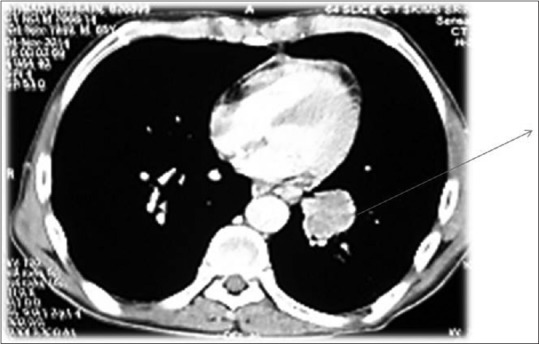

Further evaluation was carried out with imaging of chest and abdomen, along with imaging of referable sites. Contrast-enhanced computed tomography (CECT) chest and abdomen was carried out in all patients, revealing right hilar mass in 66% of patients, left hilar mass in 22%-of patients, and 12%-had right peripheral lung mass. Superior vena cava (SVC) partial or complete occlusion was seen in 33%; right-sided plural effusion, ascites, and liver metastasis was seen in 11%-each [Figures [Figures11 and and2].2]. Bronchoscopy revealed intrabronchial pathology and clinched the diagnosis in 88% of patients; rest of patients needed computed tomography (CT)-guided biopsy of lung for getting histological diagnosis. Lung biopsy was positive for napsin, cytokeratin (CK) 5/6, and negative for synaptophysin and thyroid transcription factor 1 [Figure 3]. Bone scan was positive in two patients with one uptake in iliac bone and other in Tibia [Figure 4 of X-ray Tibia]. CECT of muscle metastasis sites was done and biopsy was carried out in each patient [Figure 5]. Distribution of metastasis was unique, 66%-patients had pelvic skeletal muscle involvement, 22%-had thigh muscle, and 11%-had lower paraspinal muscle metastasis.

| Figure 1:Contrast-enhanced computed tomography chest showing left hilar mass